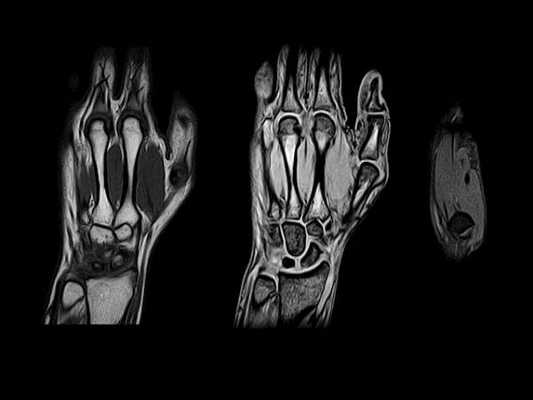

(Слева) Продольное цветовое допплеровское картирование: типичные признаки теносиновита с отчетливо повышенной васкуляризацией, указывающей на полнокровие. Также визуализируются синовиальное утолщение и гиперемия ладонного отдела капсулы сустава, указывающие на наличие синовита. Это подтверждает раннюю стадию РА при отсутствии рентгенографических изменений.

(Справа) МРТ, аксиальная проекция, режим Т2 с подавлением сигнала от жира: признаки теносиновита с сигналом высокой интенсивности, вокруг нормальных сухожилий сгибателей и разгибателей и в дистальном луче-локтевом суставе. Эрозии не визуализируются. Рентгенография не выявила патологических изменений. (Слева) МРТ, корональная проекция, режим Т1: головки пястных костей с краевыми эрозиями пациента с впервые возникшей односторонней болью и отеком. Рентгенография не выявила признаков этих эрозий.

(Справа) МРТ, корональная проекция, режим Т2 с подавлением сигнала от жира: признаки поражения за пределами пястно-фаланговых суставов у того же пациента. Визуализируются похожие признаки образования выпота, а также краевых и субхондральных эрозий костей запястья, лучезапястного и дистального луче-локтевого суставов. Распространение и характер эрозивного процесса типичны для РА. (Слева) Рентгенография в ЗП проекции: признаки отека в области ПФС и ПМФС у пациента с впервые возникшей болью и отеком кисти: признаки локального остеопороза или эрозий не визуализируются, однако отмечается расширение 2-го и 3-го ПФС. Причиной тому служат синовит и суставной выпот. Это самые ранние рентгенографические признаки РА.

(Справа) Рентгенография в ЗП проекции: юкстаартикулярная остеопения и сужение хряща в ПФС. Размытость кортикального слоя в области головок пястных костей имеет штрих-пунктирный характер, указывающий на ранние эрозивные изменения.